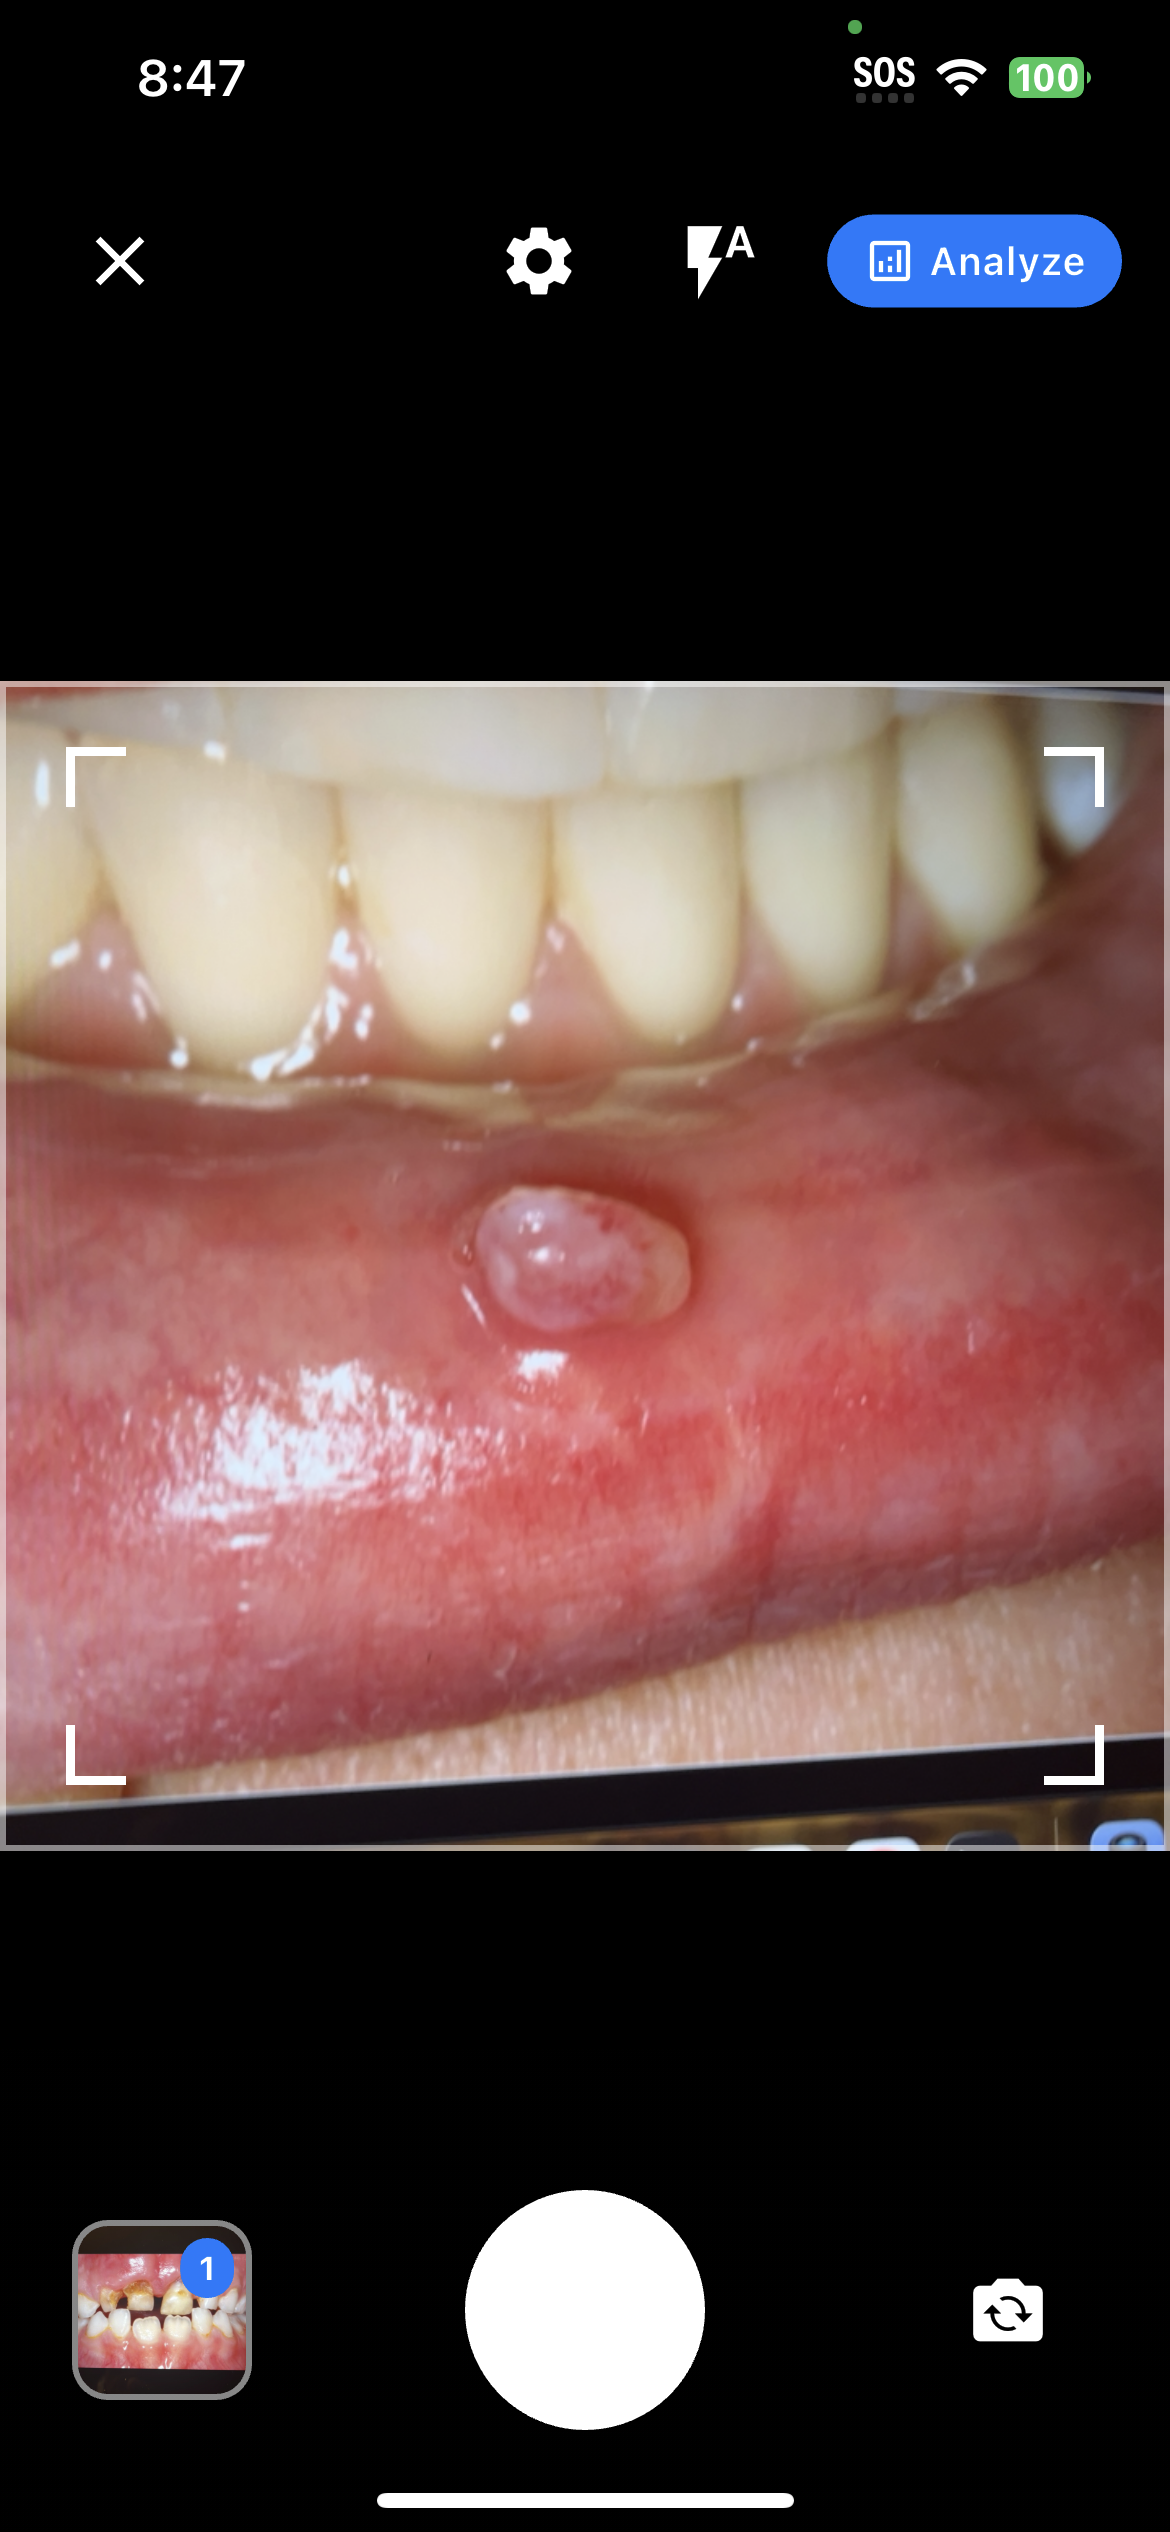

Professional Image Capture

Clinical Image Capture

Professional-grade image capture interface with quality guidelines and real-time feedback for optimal diagnostic accuracy.

AI Analysis Interface

AI Diagnostic Analysis

Real-time AI processing with detailed diagnostic insights, confidence scores, and clinical recommendations.